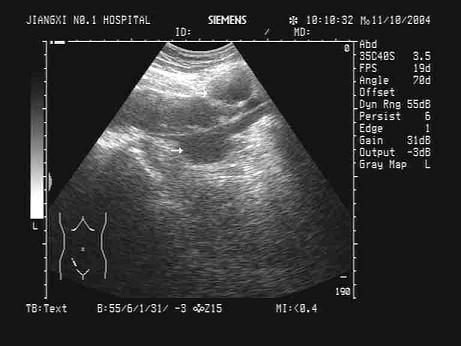

患者,胃癌手术后2年,髂窝处声像图表现如图,诊断是?(?)A.正常声像图B.肿大淋巴结C.阑尾脓肿D.肠道转移灶E.动脉瘤

问题 患者,胃癌手术后2年,髂窝处声像图表现如图,诊断是?(?)

选项 A.正常声像图 B.肿大淋巴结 C.阑尾脓肿 D.肠道转移灶 E.动脉瘤

答案 B